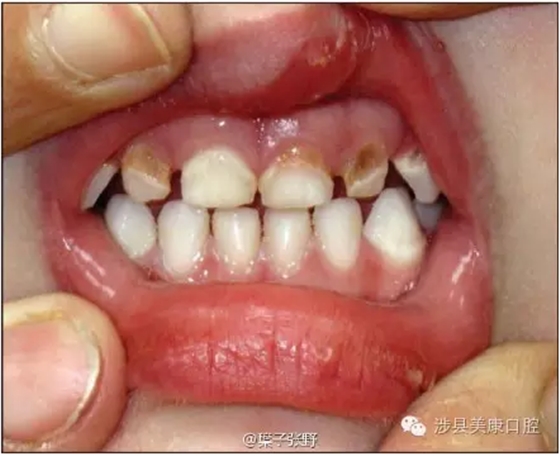

蛀牙會疼痛,非常痛。孩子可憐死了,影響吃飯。

![(VG08}R)0@])T5`)IIBPUD5.png (VG08}R)0@])T5`)IIBPUD5.png](/Mobile/UploadFiles/FCK/2017-04/6362664243054169673055611.png_280.jpg)

影響美觀,讓小朋友笑話。